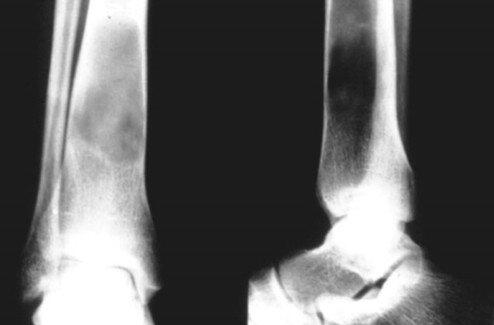

本症的诊断主要靠X线检查和病理活检。典型的骨囊肿诊断并不困难。儿童期突然发生病理性骨折,并有“落叶征”可确诊。X线检查,某长骨(肱骨上端、股骨上端)在骨骺线的偏一侧,位于干骺端的中央,有一梭形膨胀的透明阴影,其边缘由变薄的骨皮质完整的包绕,界线清楚,腔内可有不规则的骨嵴间隔则可以诊断。